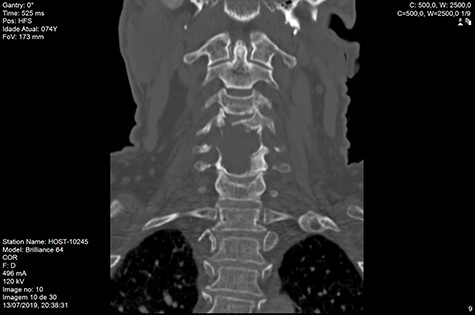

MRI and CT scans performed at 90 days post-radiation therapy showed an arrest of further progression of instability and resolution of the lytic lesion (Figs 7–13).

Although cases need to be discussed individually and surgery considered in cases of significant spinal instability or deformity and potential neurological injury, our results on this case supports the fact that isolated radiotherapy should be considered and be used to treat even extensively destructive osteolytic MM lesions to restore the structural integrity of the spinal elements.